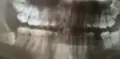

Сильно болит нижний левый зуб мудрости. Рот перестал открываться. Сегодня пойду к врачу. Была ещё вчера на приёме, готовы были удалить, но я не доверилась врачу. Есть ли воспаление в корнях?

• В области восьмого зуба справа есть периапикальное воспаление. Лечить зуб при таком расположение нецелесообразно, поэтому рекомендуют удалить. Также, восьмой зуб справа расположен горизонтально, он никогда не прорежется, только будет периодически доставлять дискомфорт.

Беспокоит нижний зуб мудрости, который вырос ровно, но под капюшоном. Врач-хирург промыл его. Глядя на снимок, сказал, что если не болит больше ничего делать не надо.

• Он практически лежит у Вас перпендикулярно зубу 4.7. Если он Вас беспокоит, то лучше удаляйте. Он вероятнее всего не прорежется.